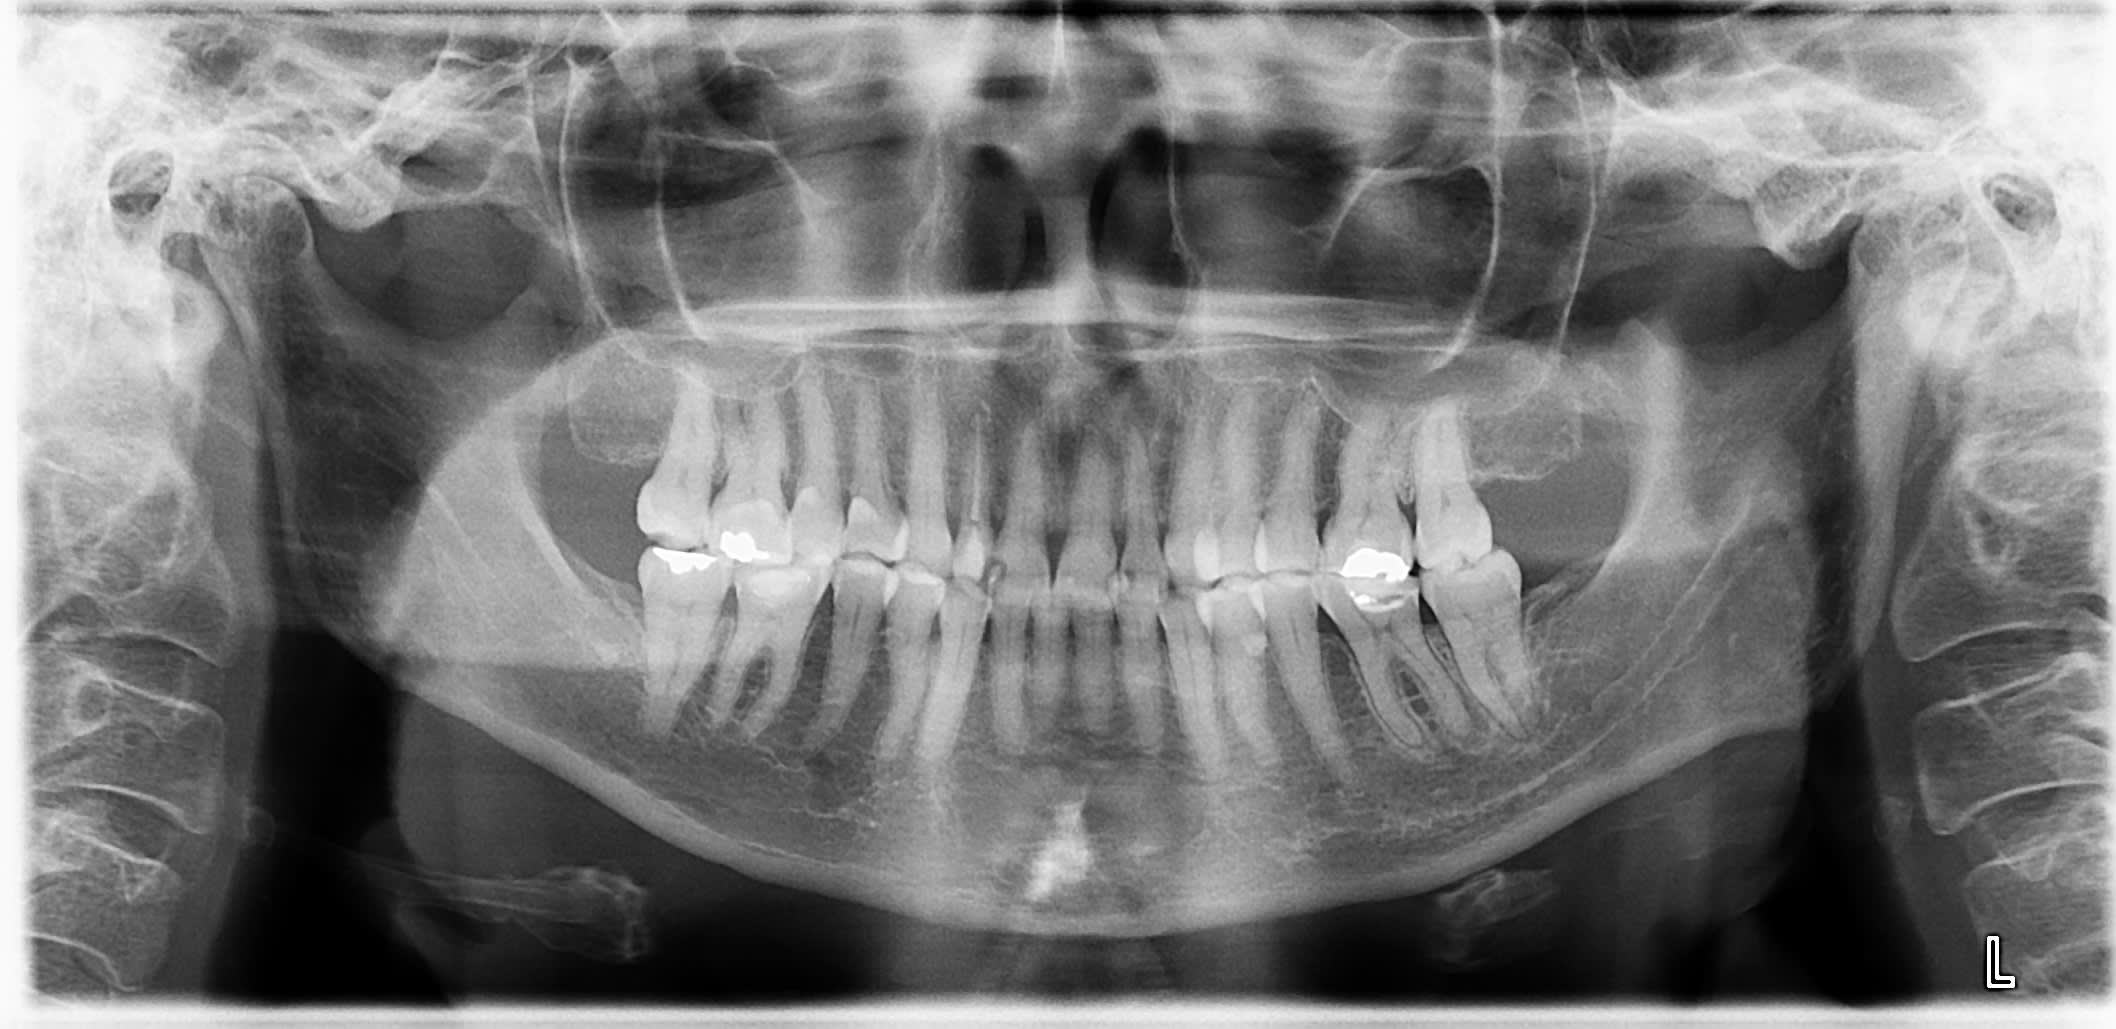

pano